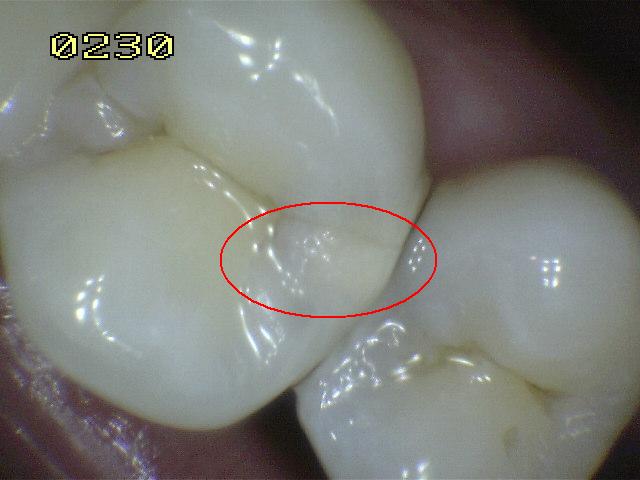

Código 4

(Caries Moderada): Sombra oscura

de dentina subyacente al esmalte intacto con o sin interrupción

localizada del esmalte

-

Esta lesión aparece como una sombra de decoloración

visible a través de una superficie de esmalte intacta, la que puede o no mostrar signos

de descomposición localizada del esmalte, como la microcavidad y /o discontinuida

< 0,5mm. después del secado con aire durante 5

segundos

La aparición de

la sombra se ve a menudo con más facilidad cuando

el diente está húmedo. El área oscura es una

sombra intrínseca que puede aparecer gris, negro-azul o

marrón-anaranjado,

a través de las paredes del esmalte vestibular, lingual o

palatino